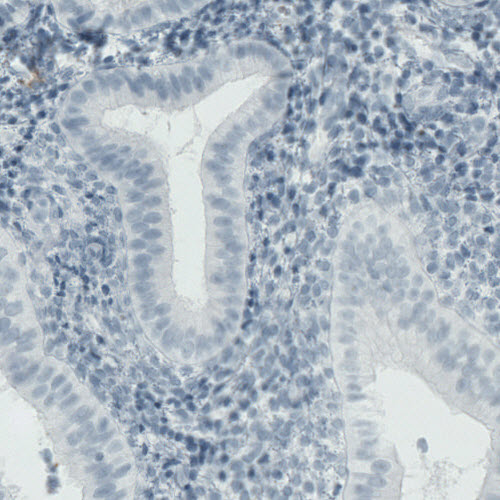

Immunohistochemical staining of human tonsil shows strong immunoreactivity in a subset of lymphoid cells, primarily outside germinal center.